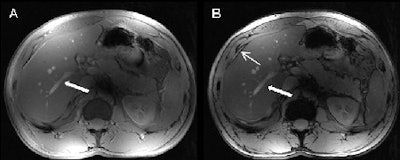

T1-weighted 2D in (A) and opposed (B) phase MRI provides conspicuity of liver vasculature (arrows) and typical sharply defined black rims around organs with a fat/water interface in the opposed phase image (slim arrow). All images courtesy of Dr. Lale Umutlu.Patient sample